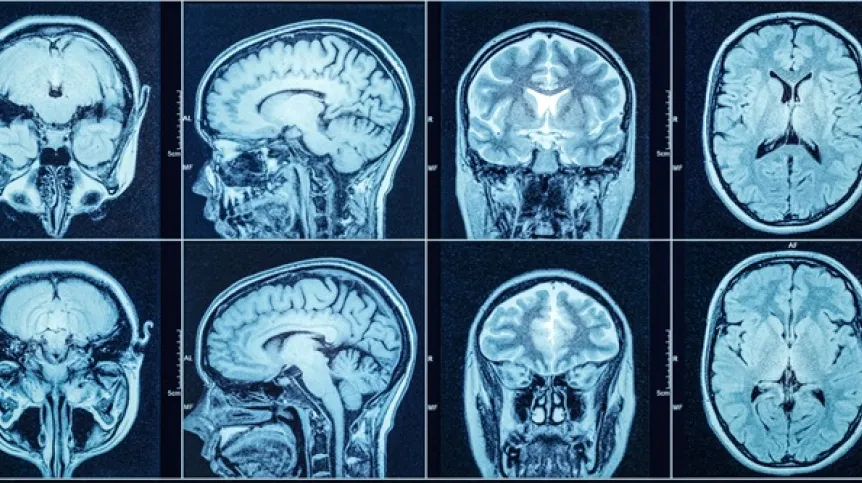

Obraz MRI nie w pełni odpowiada rzeczywistej aktywności mózgu

Widoczne na typowych obrazach mózgu z rezonansu magnetycznego (MRI) nasilenie przepływu krwi nie jest zbyt wiarygodnym wskaźnikiem zapotrzebowania energetycznego mózgu – tylko 60 proc. sygnału MRI odpowiada jego rzeczywistej aktywności - informuje “Nature Neuroscience”.

Naukowcy z Niemiec i USA odkryli, że wzmożony sygnał fMRI jest w około 40 proc. przypadków związany ze zmniejszoną aktywnością mózgu. Jednocześnie zaobserwowali obniżone sygnały fMRI w obszarach o podwyższonej aktywności.

Cytowana w materiałach prasowych pierwsza autorka publikacji, dr Samira Epp z Uniwersytetu Fryderyka Aleksandra w Erlangen-Norymberdze (FAU) podkreśla, iż „jest to sprzeczne z długoletnim założeniem, że zwiększonej aktywności mózgu zawsze towarzyszy zwiększony przepływ krwi w celu zaspokojenia wyższego zapotrzebowania na tlen. Ponieważ dziesiątki tysięcy badań fMRI na całym świecie opierają się na tym założeniu, nasze wyniki mogą prowadzić do przeciwnych interpretacji w wielu z nich”.

Prof. dr Valentin Riedl, obecnie profesor na FAU oraz dr Epp przebadali ponad 40 zdrowych osób. Każdej z nich polecono wykonanie kilku eksperymentalnych zadań – takich jak obliczenia w pamięci czy przywoływanie wspomnień autobiograficznych – które, jak wiadomo, powodują przewidywalne zmiany sygnału fMRI w rozproszonych obszarach mózgu. Podczas tych eksperymentów naukowcy jednocześnie mierzyli rzeczywiste zużycie tlenu za pomocą nowatorskiej techniki ilościowego MRI.

W zależności od zadania i obszaru mózgu, fizjologiczne wyniki były zróżnicowane. Zwiększone zużycie tlenu – na przykład w obszarach zaangażowanych w obliczenia – nie pokrywało się z oczekiwanym wzrostem przepływu krwi. Analizy ilościowe wykazały natomiast, że obszary te zaspokajały swoje dodatkowe zapotrzebowanie na energię, pobierając więcej tlenu z niezmienionego dopływu krwi. W ten sposób efektywniej wykorzystywały tlen dostępny we krwi, bez konieczności zwiększenia jej przepływu.

Według Riedla wnioski te wpływają również na interpretację wyników badań nad zaburzeniami działania mózgu: „Wiele badań fMRI dotyczących chorób psychicznych lub neurologicznych – od depresji po chorobę Alzheimera – interpretuje zmiany przepływu krwi jako wiarygodny sygnał niedoczynności lub nadczynności neuronów. Biorąc pod uwagę ograniczoną trafność takich pomiarów, należy to teraz ponownie ocenić. Szczególnie w grupach pacjentów ze zmianami naczyniowymi – na przykład spowodowanymi starzeniem się lub chorobami naczyniowymi – zmierzone wartości mogą odzwierciedlać przede wszystkim różnice naczyniowe, a nie deficyty neuronów” - mówi.

Naukowcy proponują uzupełnienie konwencjonalnego podejścia MRI pomiarami ilościowymi. W dłuższej perspektywie takie połączenie mogłoby stanowić podstawę modeli mózgu opartych na energii: zamiast przedstawiać mapy aktywacji zależne od założeń dotyczących przepływu krwi, przyszłe analizy mogłyby wyświetlać wartości wskazujące, ile tlenu – a tym samym energii – jest faktycznie zużywane na przetwarzanie informacji. Otwiera to nowe perspektywy badania chorób związanych ze starzeniem się, chorobami psychicznymi lub neurodegeneracyjnymi w kontekście bezwzględnych zmian metabolizmu energetycznego – i ich dokładniejszego zrozumienia.